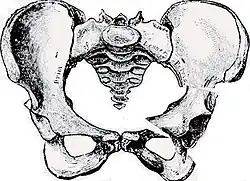

- Beckenanatomie

Anatomie des gesunden Beckens (Ansicht von vorne) -

Modell eines gesunden Beckens

Das Becken ist der Mittelpunkt des menschlichen Körpers und vereinigt die Wirbelsäule mit der unteren Extremität (Bein). Gleichzeitig liegen wichtige Organe, wie z. B. die Harnblase, der Enddarm, die Geschlechtsorgane und deren Anhänge, direkt im Beckengewölbe. Große Gefäße und Nerven (Ischiasnerv, Beckenarterie und -vene) gabeln sich hier. Schließlich setzen zahlreiche Muskeln, Sehnen und Bänder am Becken an, die für die Körperstatik und besonders für die komplexen Hüftbewegungen wichtig sind.

Die gewölbeartige Struktur des Beckens und die empfindlichen Weichteilverhältnisse (Nerven, Gefäße, Muskel-Sehnenansätze) machen die Zugangswege kompliziert.